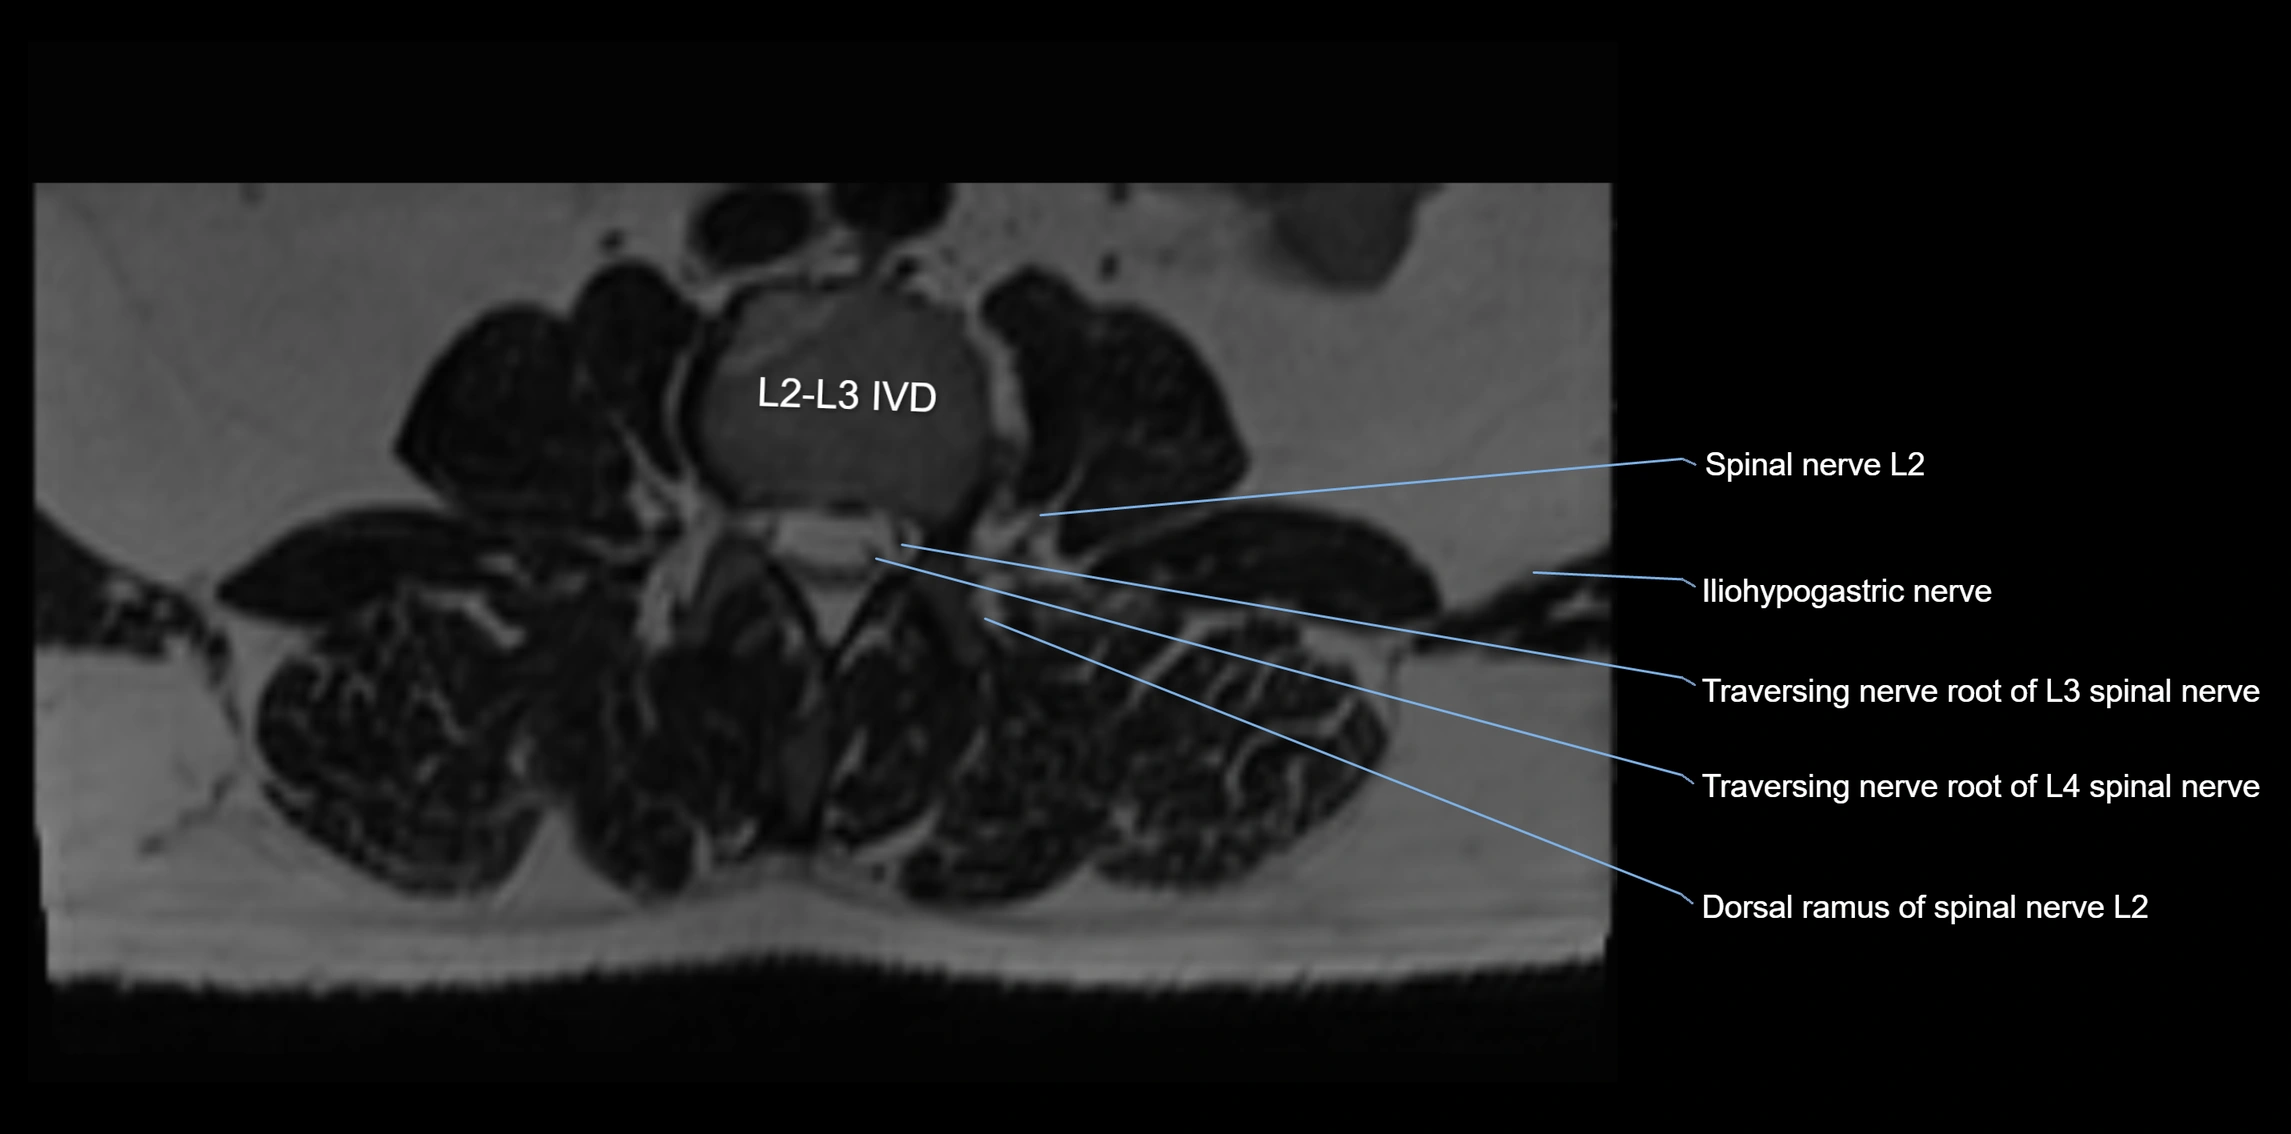

MRI Appearance

T1-weighted images:

• Nerve appears as a very thin low-to-intermediate signal intensity structure

• Surrounded by bright fat, aiding visualization

T2-weighted images:

• Nerve shows intermediate to mildly hyperintense signal compared to muscle

• Pathological involvement appears brighter

STIR (Short Tau Inversion Recovery):

• Normal nerve appears dark

• Inflamed or entrapped nerve appears bright hyperintense

T1 Fat-Sat Post-Contrast:

• Normal nerve enhances minimally

• Pathologic nerve (neuritis, entrapment, tumor infiltration) shows focal or diffuse enhancement

3D T2 SPACE / CISS:

• Nerve appears intermediate to mildly hyperintense compared to muscle

• Surrounded by bright fat or CSF, improving visualization

• Best sequence for mapping small pelvic nerves such as the anococcygeal